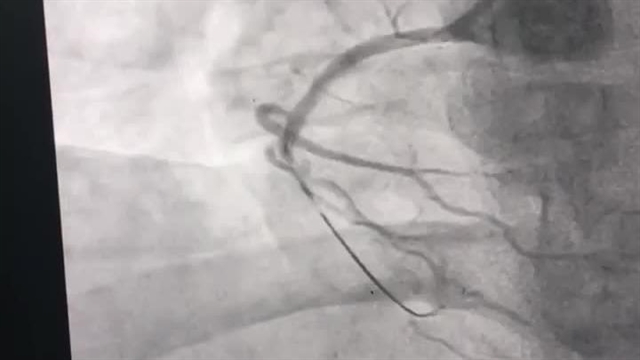

متخصص قلب دکتر محسن فقیهی نیا ساری

بهترین دکتر فوق تخصص قلب ساری را از میان بهترین متخصصین قلب و عروق ساری پیدا کنید . ما در این مطلب لیستی از بهترین دکترهای فوق تخصص قلب را معرفی میکنیم .قلب یکی از حیاتی ترین عضو بدن بوده که در صورت آسیب دیدن جان انسان را به خطر می اندازد . با توجه به مهم بودن این موضوع باید سعی شود در صورت بروز هر بیماری یا مشکلی در این ناحیه از بدن به پزشک مراجعه کنید .